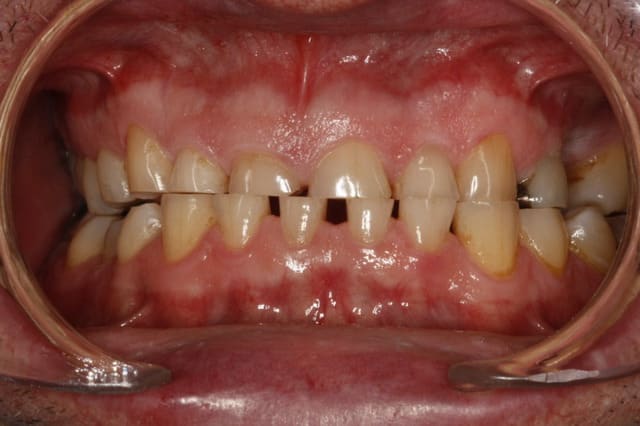

Tu penses quoi de ce patient, 50 ans.

Perte de DV ou non ?

Je restore comme cela ou bien je dois ouvrir 1-2 mm ?

Je laisse comme cela ?

--

Céramik